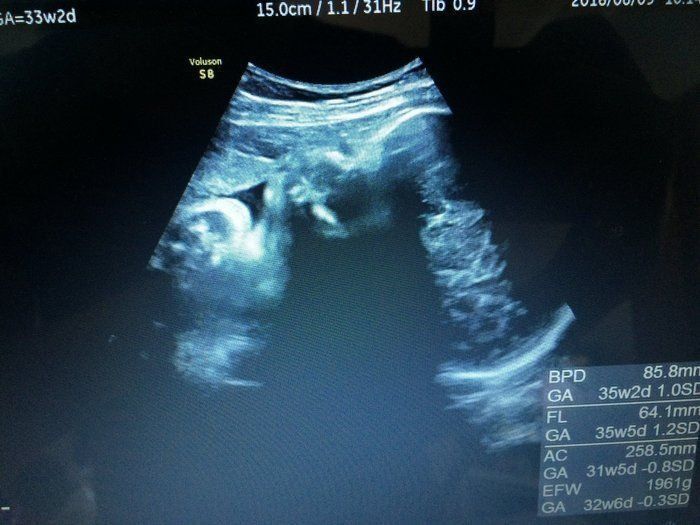

Tomomiさんの妊娠33週目のエコー写真 推定体重1961g 未熟児だったママの出生体重を超えた!

ついに妊娠9カ月目に突入。娘の抱っこ攻撃もそろそろ腕が限界になり、ついついおなかの上に娘を乗せてしまいがち。おなかの中から「重いよ!」と聞こえてきそうなくらい胎動も激しく、良く耳にする“男の子の子育ては体力勝負”を薄々実感しながら、産後に不安を感じる33歳の夏でした。